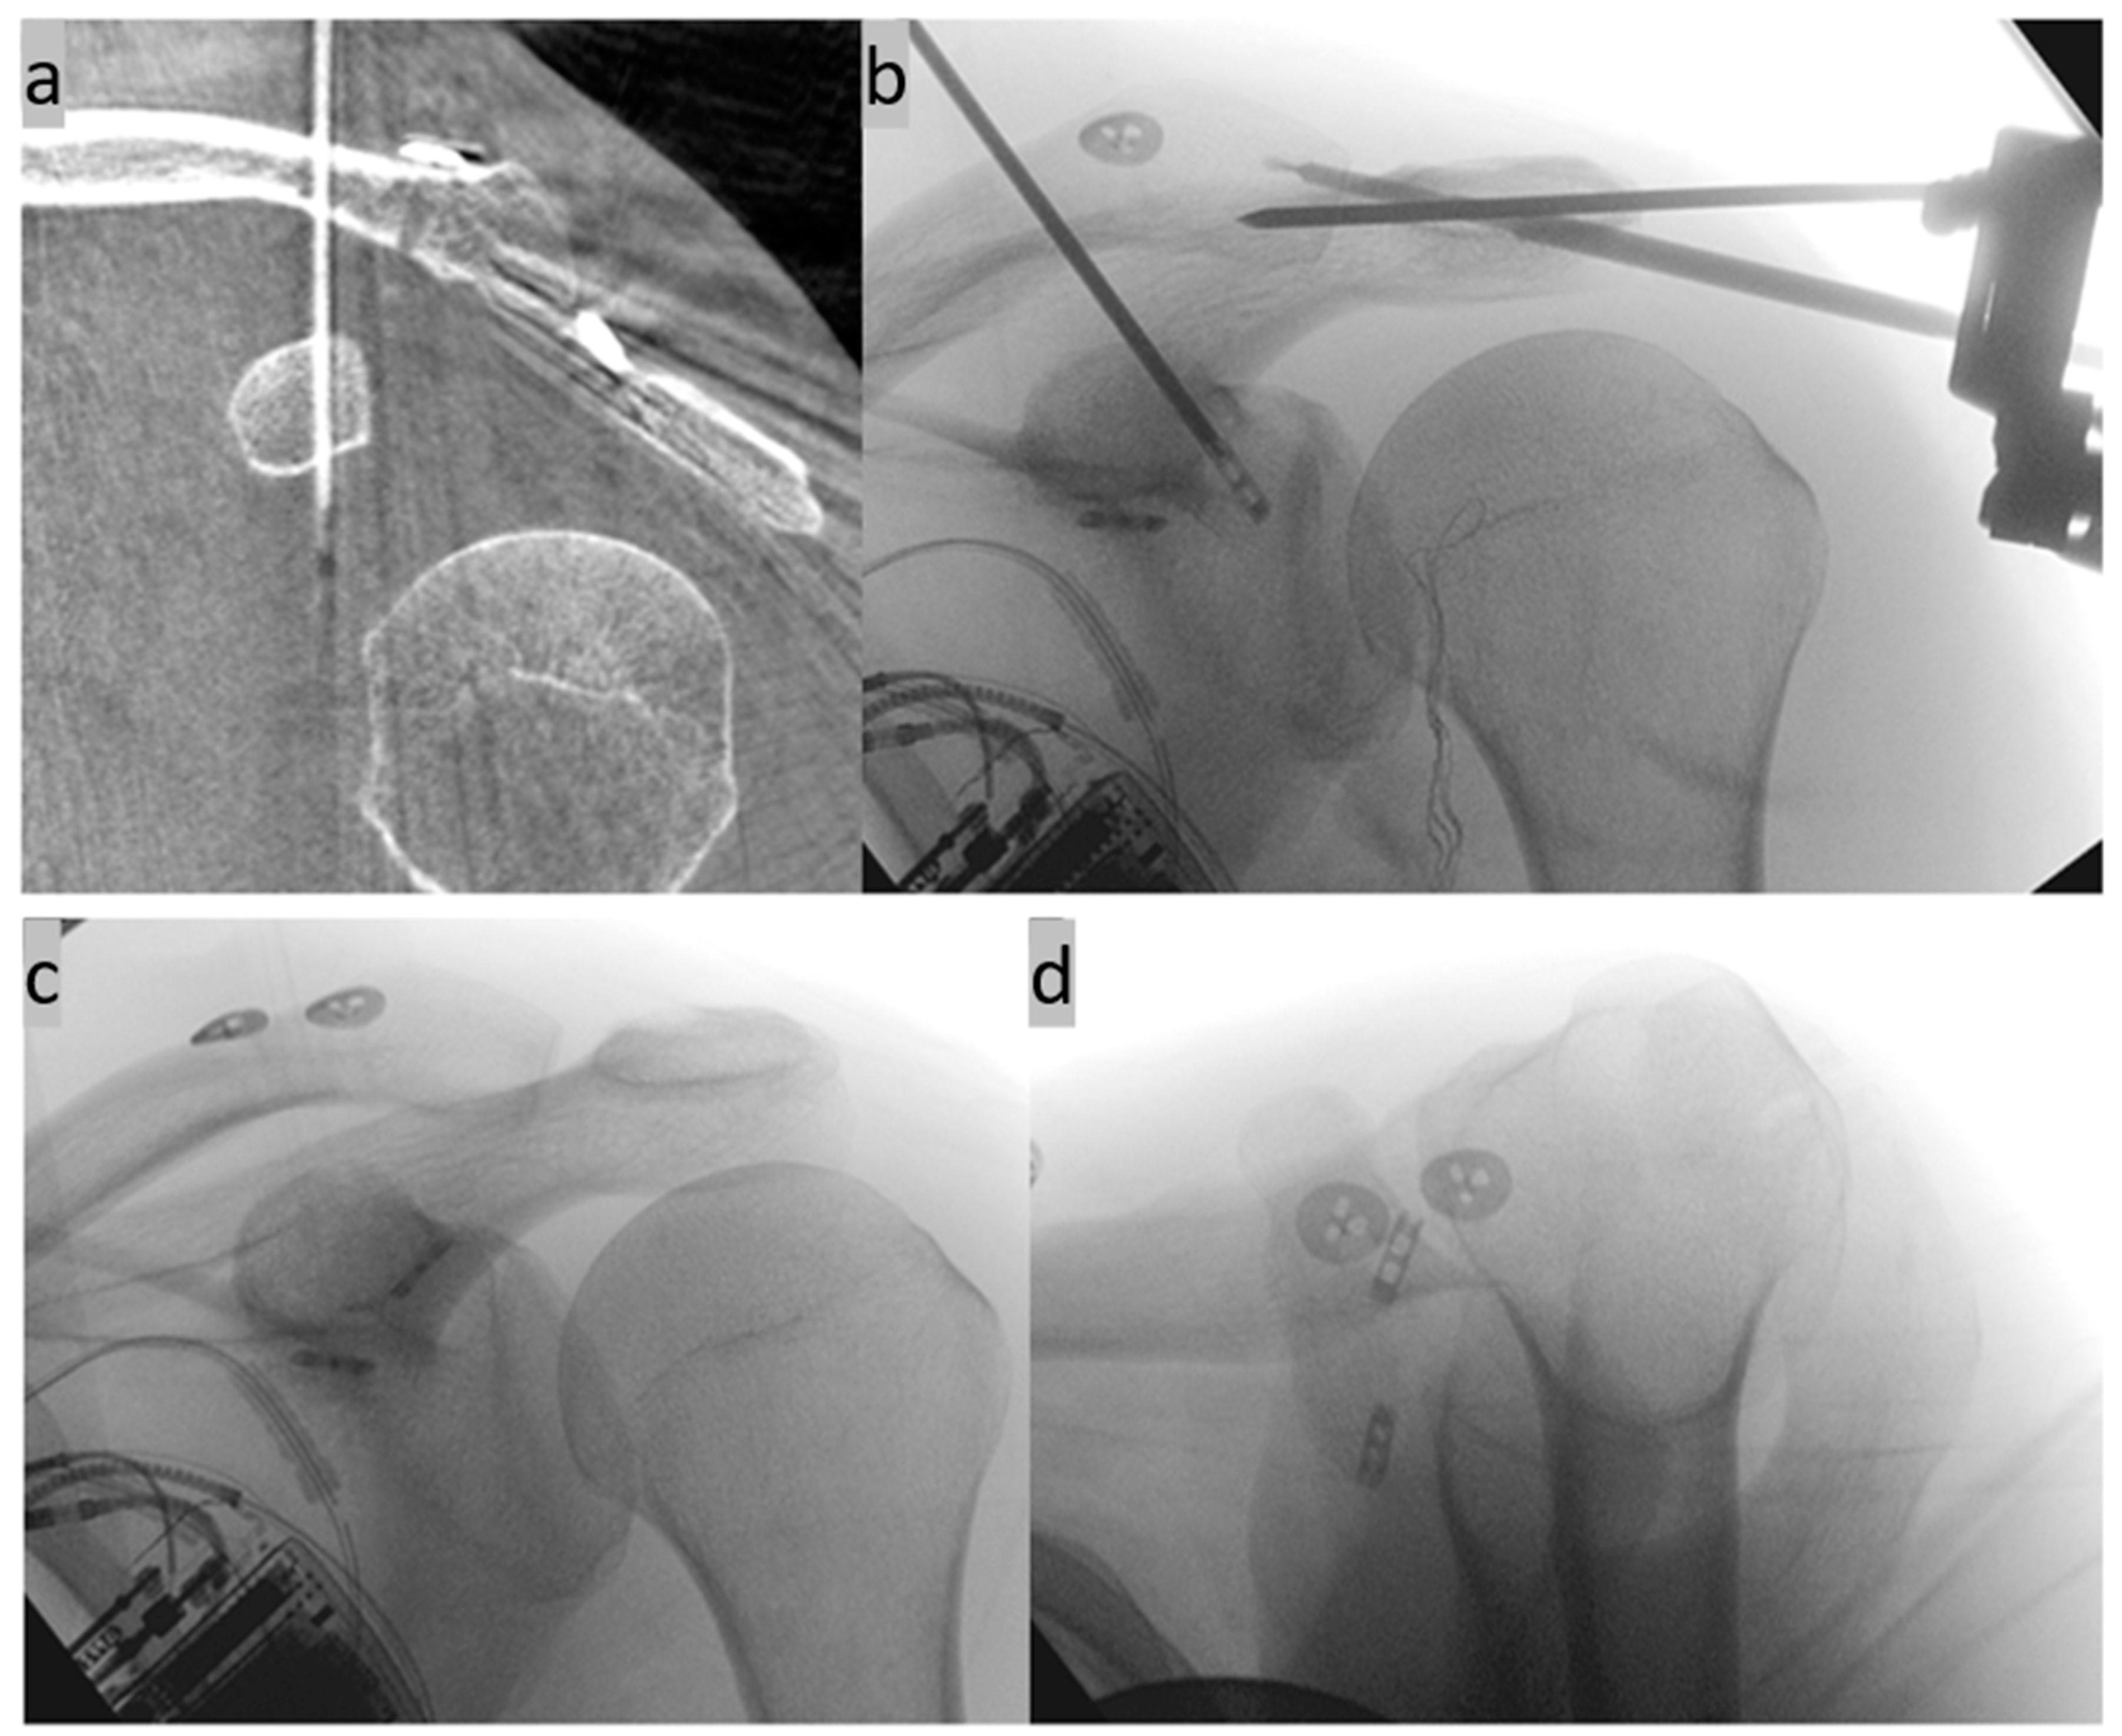

2. Surgical Technique

- Böhringer, A.; Gebhard, F.; Dehner, C.; Eickhoff, A.; Cintean, R.; Pankratz, C.; Schütze, K. 3D C-arm navigated acromioclavicular joint stabilization. Arch. Orthop. Trauma. Surg. 2023, 144, 601–610. [Google Scholar] [CrossRef]